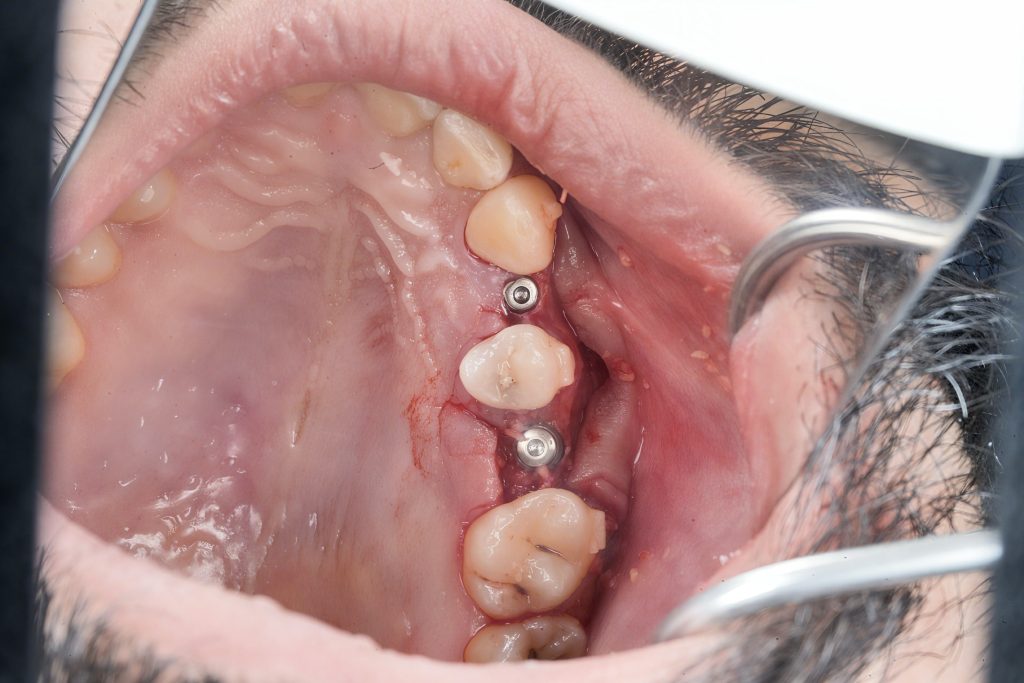

Under local anesthesia, a full-thickness mucoperiosteal flap was raised. Sequential osteotomy drills were performed up to 1 mm short of the sinus floor. Osteotomes of increasing diameters were used to carefully fracture the sinus floor through controlled malleting, lifting the Schneiderian membrane atraumatically (Fig 2).